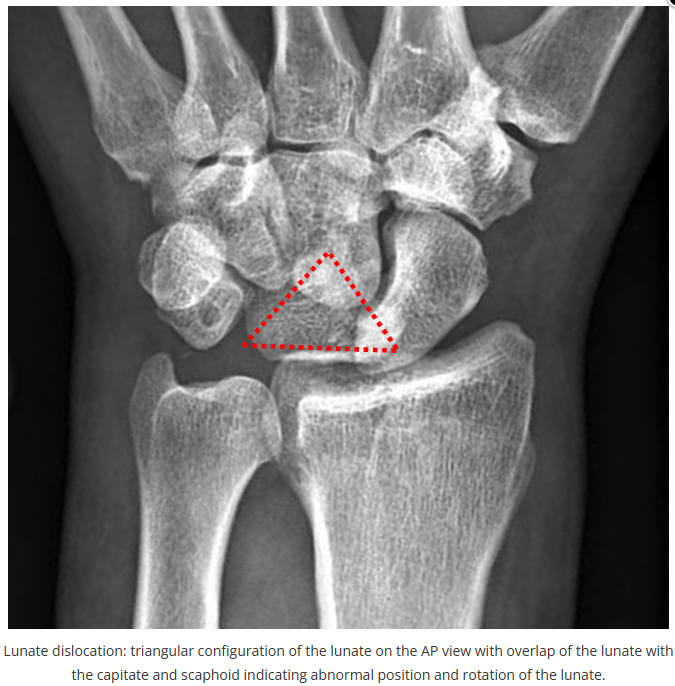

这些腕与手的骨折X线片如果没有标注箭头,你还能识别出来吗?

X线读片是骨科医生的基本功。

今天是腕部与手的X线片。所有X线片都

带有标注和说明

,可以选择长按图片,

自动翻译相关说明

。